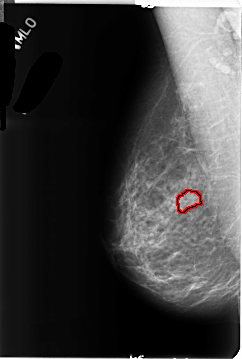

B_3132_1.RIGHT_MLO

RIGHT_MLO LINES 4664 PIXELS_PER_LINE 3136 BITS_PER_PIXEL 12 RESOLUTION 50 OVERLAY

FILE: B_3132_1.RIGHT_MLO.OVERLAY

TOTAL_ABNORMALITIES 1

ABNORMALITY 1

LESION_TYPE MASS SHAPE OVAL MARGINS CIRCUMSCRIBED

ASSESSMENT 3

SUBTLETY 3

PATHOLOGY BENIGN

TOTAL_OUTLINES 1

BOUNDARY